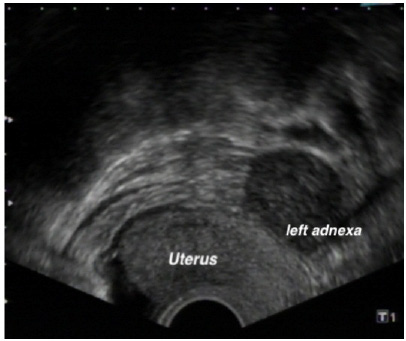

Figure 1: Ultrasonographically, there is a 4.5x4 cm large, well-defined and homogeneous mass on the left adnexa.

figure 1